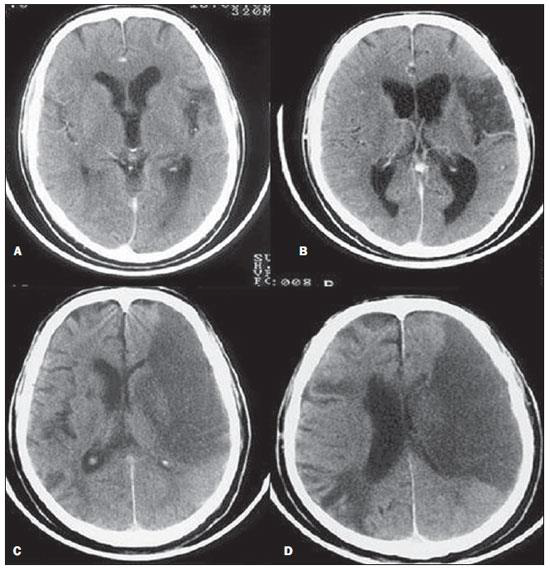

Observe a imagem tomográfica abaixo, analise os excertos e assinale a alternativa correta:

http://www.rb.org.br/detalhe_artigo.asp?id=2613&idioma=Portugues

I – Tomografia Computadorizada com AVCI do território da Artéria Cerebral Posterior (ACP).

II – A;B - Infarto parcial, com envolvimento restrito ao hemisfério esquerdo.

III – C;D: Infarto completo à esquerda, com efeito de massa comprimindo o ventrículo lateral.

IV - No hemisfério direito visualiza-se hipodensidade esquerda maior.

Está correto o que se afirma em: